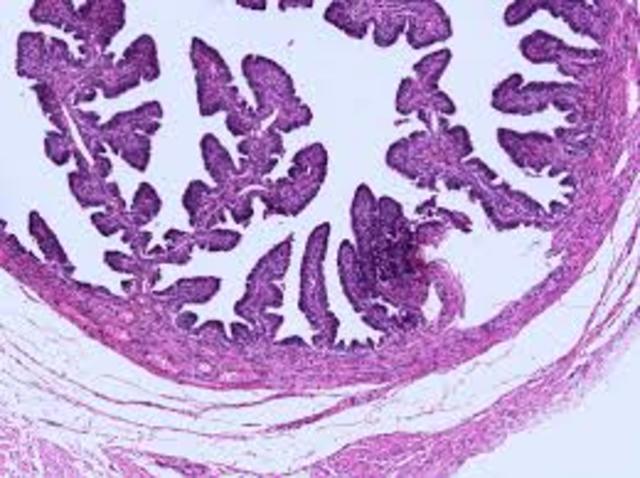

• Histology Microscopes Lab

Histology Microscopes Lab

In pairs, students will visit the online resource and individually draw the specific image as displayed and the magnification it is viewed from. Additionally they will visit the correlating microscope and view it through there as well. Students will have 100 minutes to draw, color and identify all tissues online and from the microscopes in class.

Flip cards

Students will be given 12 pictures of tissues of the body. They will be expected to know them all for the unit exam. students will idenitfy using their resource materials, given by teacher, online computer resources, including lectures. They will also color them appropriate colors. 50 minutes